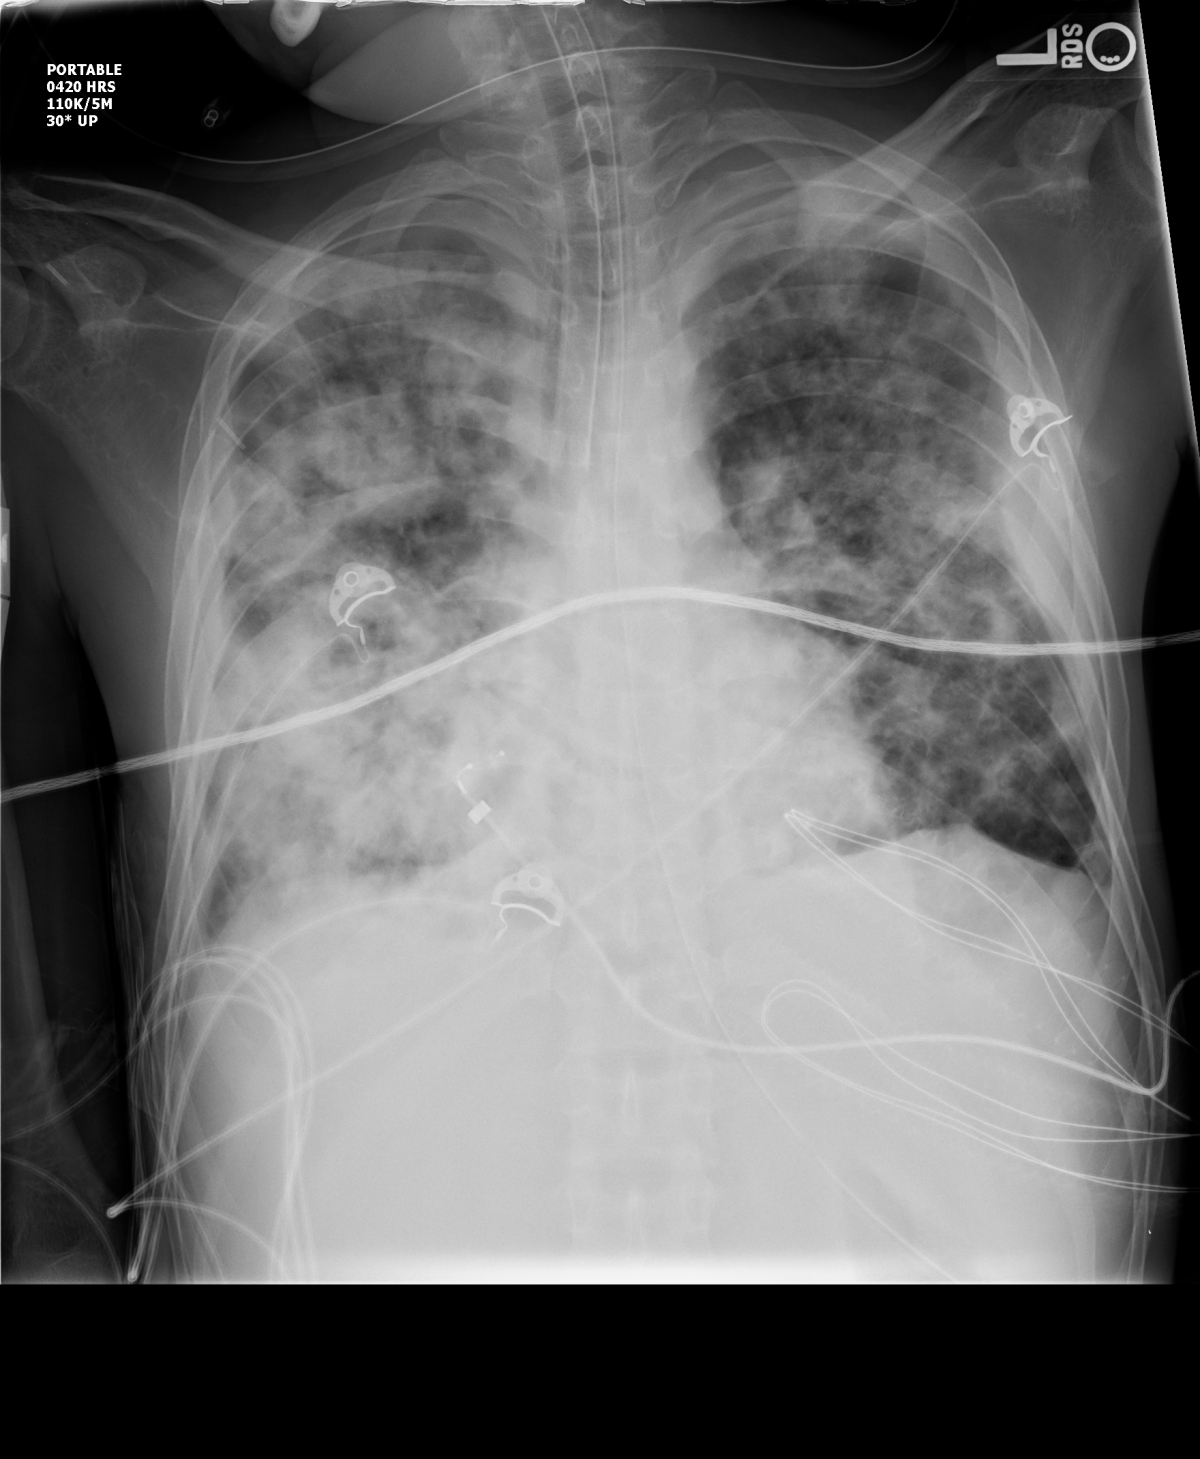

It’s not just suffocation from respiratory failure, as the lungs fill with fluid such as the chest X ray above. It’s the multiple organ failure that gets you too. I added the 2nd, 3rd, and 4th pressor. Nothing helped. I watched as the ventilator tubing filled with blood pouring from her lungs. Tried steroids. Tried statins. Tried anti-parasiticals. Nothing worked.

**The above CXR is not my patient, due to HIPPA laws. That patient’s CXR was worse. And yes, the endotracheal tube is too far down and needs to be retracted.